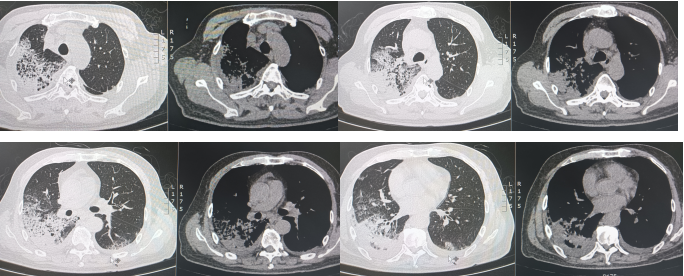

2024年8月21日急诊科胸部CT示:双肺散在炎症(右肺为著)(图1),入院后辅助检查示:白细胞计数10.09×109/L,中性粒细胞绝对数8.06×109/L,C反应蛋白119.34 mg/ml,降钙素原0.096 ng/ml,血清淀粉样蛋白>288.00 mg/L,红细胞沉降率测定96 mm/h,白介素-6 40.88 pg/ml;其余凝血功能、外周血淋巴细胞亚群、血生化、尿常规、粪便常规、心功能、肿瘤标志物、甲状腺功能、呼吸道病原体抗体、多重病原体核酸、支原体、衣原体核酸均未见明显异常。床旁气管镜示:右主支气管及各级支气管可见少许黄白色黏稠痰,以右肺下叶基底段为甚,予以灌洗后吸引并送检。左主支气管及各级支气管可见少许黄白色黏稠痰,以左肺下叶为甚,予以灌洗后吸引并送检。肺泡灌洗液(BALF)涂片、培养、GM试验、分枝杆菌检测、Xpert:(-);BALF NGS结果:流感嗜血杆菌(序列数15)。